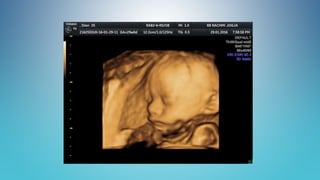

Jika kalian melihat gambar ini,

Apa makna yang kalian tangkap ?

Menurut kalian,

gambar apakah ini

?